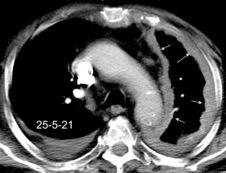

Tromboembolismo pulmonar.

Frecuencia del derrame:

Rx: 32%. TC: 47%

Unilateral. 85%

< 1/3 del hemitórax: 90%

Todos exudados

58% con eritrocitos

21% tabicación lo que causa demora en el diagnóstico

TEP. Empiema pleural. Atelectasia redonda

Porcel JM et al. Analysis of pleural effusions in acute pulmonary embolism: radiological and pleural fluid data from 230 patients. Respirology 2007/ Iguchi T et al. Desquamation of the subpleural lung parenchyma caused by empyema after pulmonary embolism: A case report. Respirol Case Rep. 2022 .